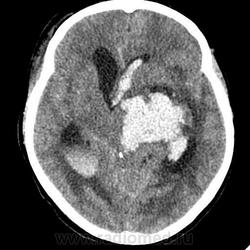

Острое внутримозговое кровоизлияние с выходом крови в желудочки (боковые - сгустки преимущественно в левом + эффект седиментации с горизонтальным уровнем жидкость\жидкость в задних рогах; сгустки крови в третьем желудочке, кровь в четвертом). Значительное увеличение височных рогов боковых желудочков - гидроцефалия. Смешение срединных структур вправо, отек белого вещества перивентрикулярно слева.

Довольно большие кровоизлияния в стволе мозга (что объясняет тяжесть состояния).

Я написала отек мозга, острое массивное (около 100 мл только внутримозговое) смешанное кровоизлияние слева + в стволе, с прорывом и гемотампонадой желудочков, выраженной латеральной дислокацией (13 мм), менингиома? лобного полюса слева. Убедительных данных за опухоль, давшую кровоизлияние, не вижу, хотя такая мысль тоже была.  Контрастировать такую пациентку никто не будет, агонизирующая(.

У, сколько всего написано. Пока не пришла Nela, поучаствую и я. 1. Кровоизлияние в ткань мозга, а не в опухоль: а)не видно ткани опухоли; б) неясна первичная локализация опухоли (левые базальные ядра?!); в)нет перифокального отека вокруг предролагаемой опухоли, г) при опухолях прорывы в желудочки - редкость; 2) к поперечной дислокации добавил бы безесловную аксиальную: даже цистерна моста сужена, не говоря уже про обходную-четверохолмную и другие; 3) менингиома в левой лобной области, на мой взгляд, сомнительна (кстати, покажите ее пожалуйста), ИМХО - "игра" плотностей;  4) ///метастазы в сосудистые сплетения/// - это очень круто, но они не дали бы внутримозгового кровоизлияния, как и ///плексуспапилома///.

Массивное медиальное кровоизлияние с прорывом в желудочки. Кровоизлияние в ствол. Признаки вклинения. В лбу может что-то и есть, но это не принципиально. А может быть и отечные извилины. Смущает, что нет масс-эффекта.

Причина таких кровоизлияний, как правило, гипертензия и атеросклероз.